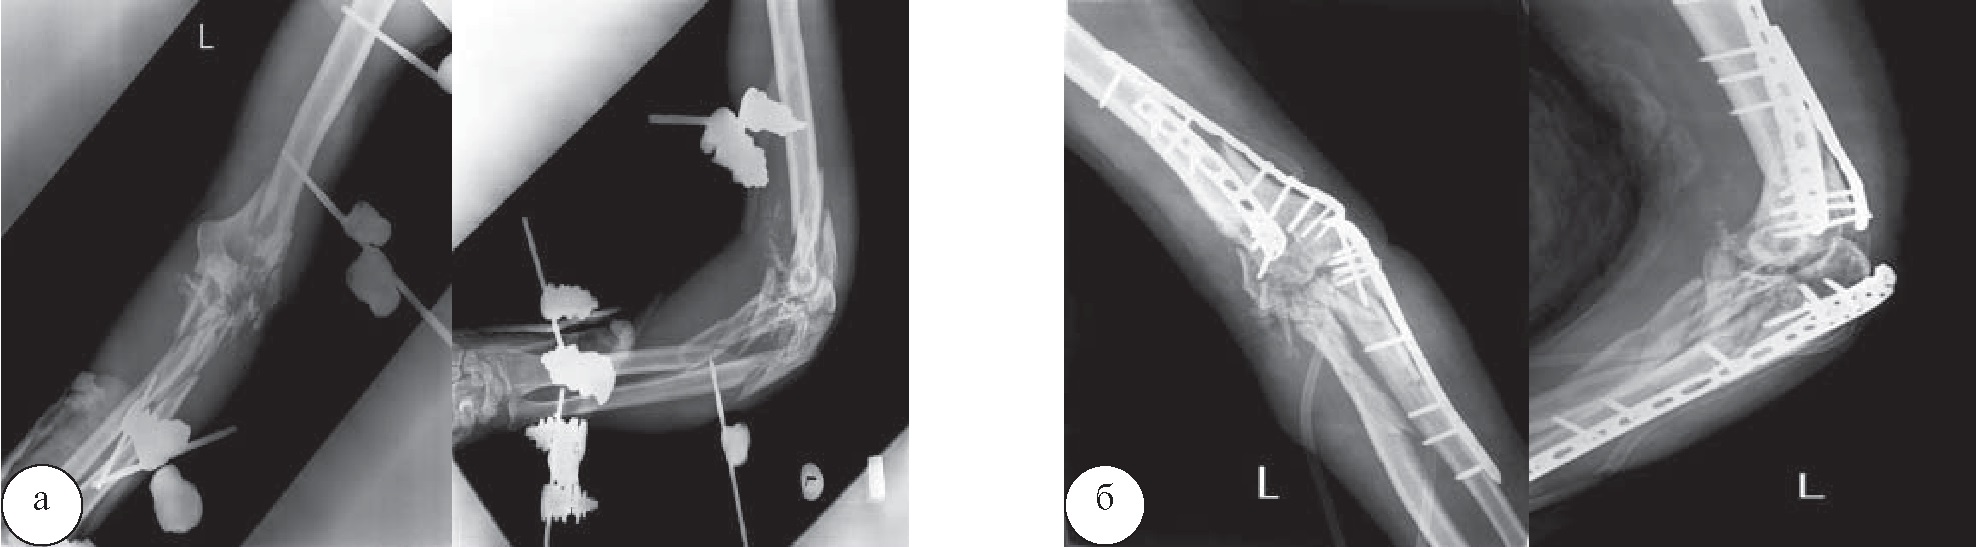

Рис. 4. Рентгенограммы левой бедренной кости пациента М.: а – неправильно срастающийся фрагментарный перелом верхней трети левой бедренной кости, фиксированный стержневым аппаратом внешней фиксации; б – после операции – остеосинтеза интрамедуллярным гвоздем с блокированием и аугментацией пластиной

Рис. 5. Рентгенограммы левого плеча и предплечья пациента Р.: а – огнестрельный внутрисуставной многооскольчатый перелом дистального метаэпифиза плечевой кости, проксимального метаэпифиза костей предплечья, фиксированный стержневым аппаратом внешней фиксации; б – после операции – последовательного остеосинтеза плечевой кости двумя пластинами, локтевой кости – пластиной